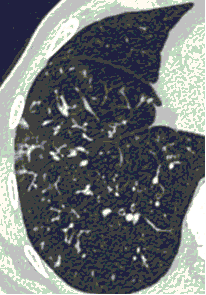

КТ имеет высокую чувствительность в выявлении изменений в легких, характерных для COVID-19. Применение КТ целесообразно для первичной оценки состояния ОГК у пациентов с тяжелыми прогрессирующими формами заболевания, а также для дифференциальной диагностики выявленных изменений и оценки динамики процесса. КТ позволяет выявить характерные изменения в легких у пациентов с COVID-19 еще до появления положительных лабораторных тестов на инфекцию с помощью МАНК. В то же время, КТ выявляет изменения легких у значительного числа пациентов с бессимптомной и легкой формами заболевания, которым не требуется госпитализация. Результаты КТ в этих случаях не влияют на тактику лечения и прогноз заболевания при наличии лабораторного подтверждения COVID-19. Поэтому массовое применение КТ для скрининга асимптомных и легких форм болезни не рекомендуется. При первичном обращении пациента с подозрением на COVID-19 рекомендуется назначать КТ только при наличии клинических и инструментальных признаков дыхательной недостаточности (SpO2 < 95%, ЧДД > 22).

3. Применение лучевых методов у пациентов с симптомами ОРВИ легкой степени тяжести и стабильном состоянии пациента, возможно только по конкретным клиническим показаниям, в том числе при наличии факторов риска, при условии достаточных технических и организационных возможностей. Методом выбора в этом случае является КТ легких по стандартному протоколу без внутривенного контрастирования или РГ при ограниченной доступности КТ. Использование УЗИ в этих случаях нецелесообразно. Применение КТ исследования в сроки ранее 3 - 5 дней с момента появления симптомов заболевания, а также при отсутствии клинических проявлений поражения бронхолегочной системы является нецелесообразным. Выполнение КТ целесообразно при наличии клинических и инструментальных признаков дыхательной недостаточности (SpO2 < 95%, ЧДД > 22), либо при дифференциальной диагностике с другим заболеванием.